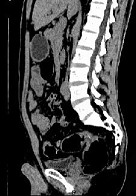

- 单项选择题女,51岁, 腹胀、腹痛、进行性消瘦,影像检查如下图, 最佳诊断是 ( )

A、乙状结肠Crohn病

B、乙状结肠结核

C、乙状结肠癌

D、乙状结肠淋巴瘤

E、乙状结肠息肉